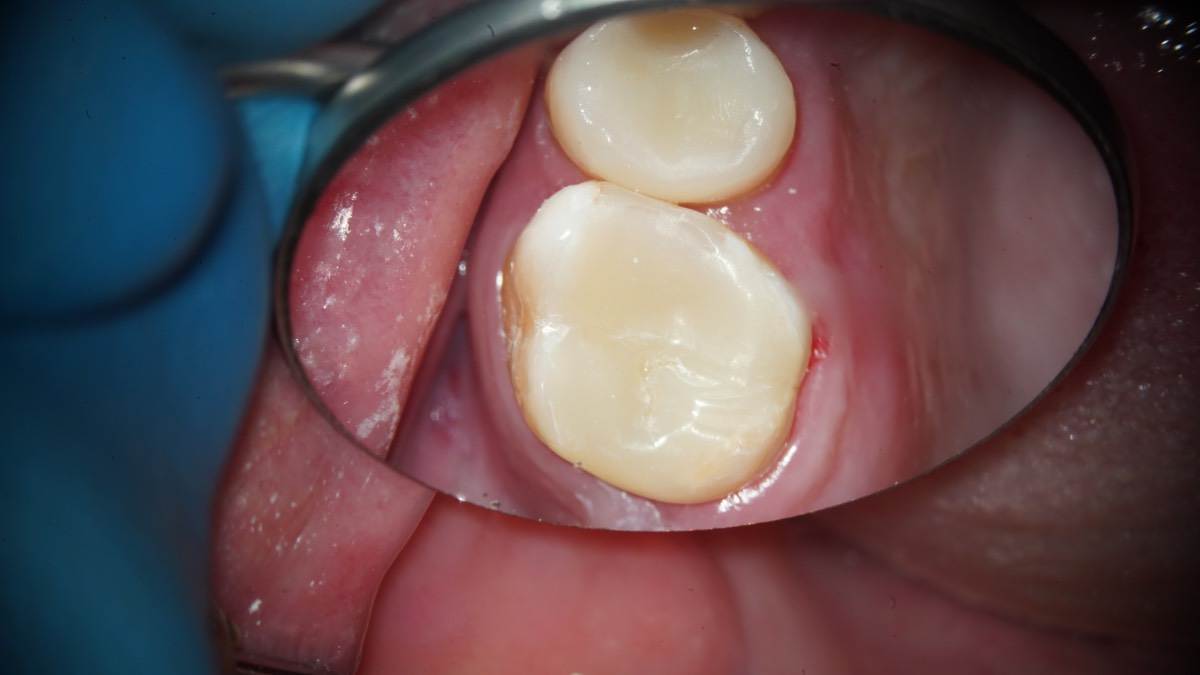

Гарриевич Опубликовано 18 марта Автор Поделиться Опубликовано 18 марта В 13.03.2026 в 15:26, Doc сказал: Круто! То, что вынимается, доктору вернуть надо или в металлолом сдать? :))) Обычно мы сдаем в чернмет, какие никакие деньги)) Реколл 3 года 1 Ссылка на комментарий

Гарриевич Опубликовано 3 апреля Автор Поделиться Опубликовано 3 апреля Еще один осмотр спустя 3 года и полное заживление 2 1 Ссылка на комментарий